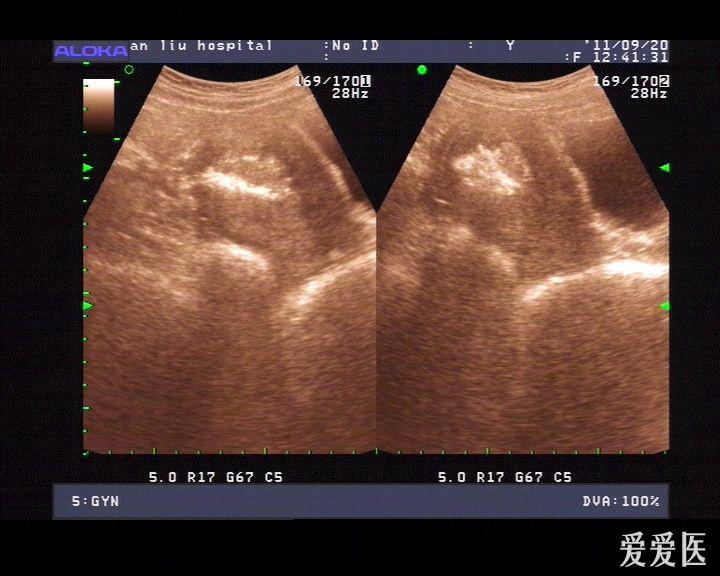

子宫穿孔的超声诊断

超声典型病例子宫穿孔

子宫穿孔彩超下表现

子宫穿孔彩超图